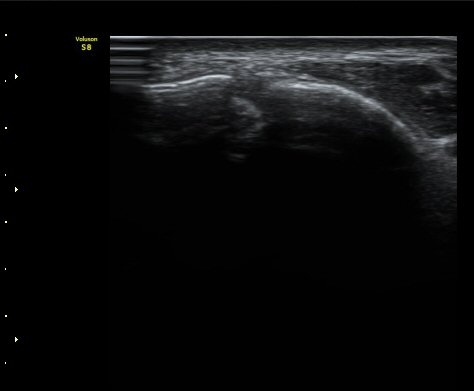

Àü°Å°ñºñ°ñÀδë Á¾´Ü¸é°Ë»ç¿¡¼­ ÀδëÀÇ ÀüÃþÆÄ¿­°ú ºÎÁ¾ÀÌ °üÂûµÈ´Ù(±×¸² 3, 4).

°ÇÃø(±×¸² 5)°ú ºñ±³ÇØ º¸¸é È¯ÃøÀÇ ÀÎ´ë ¼Õ»óÀÌ ¶Ñ·ÈÇÏ´Ù.